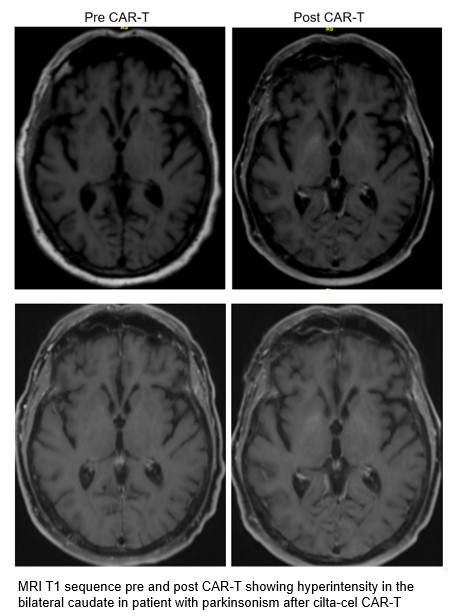

Results: A 78-year-old man presented with one month of slowness and abnormal gait after cilta-cel CAR-T therapy (post-infusion day 81) for relapsed multiple myeloma. Right facial weakness was reported post-infusion day 91. Neurologic exam demonstrated prominent hypomimia and bradyphrenia along with asymmetric rigidity, bradykinesia, and a parkinsonian gait. A lower motor neuron pattern right facial nerve palsy was also seen. MRI brain demonstrated bilateral T1 basal ganglia hyperintensity compared to MRI prior to CAR-T therapy [figure1]. Cerebrospinal fluid was without evidence of infection or malignancy. The patient was treated with cyclophosphamide, intravenous immunoglobulin, and methylprednisolone.

Conclusion: This is the first reported case of a patient with both parkinsonism and cranial neuropathy after cilta-cel CAR-T therapy. This is also the first case with abnormal MRI findings of basal ganglia T1 hyperintensity. This case highlights the importance of recognizing parkinsonism as a possible delayed neurotoxicity related to cilta-cel CAR-T. As these symptoms may emerge months after therapy, it is conceivable that this could mimic neurodegenerative parkinsonism. Recognition of atypical features such as cranial neuropathy and abnormal brain MRI may assist in diagnosis. Further investigations are needed examining imaging abnormalities in other cases. Further study is also needed as to treatment approach and outcomes.

Figure 1